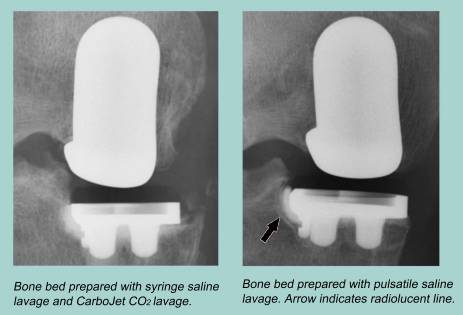

カーボジェットは人工関節置換術(TKA、UKA等)の骨セメント使用時に清掃、乾燥を行う器械。

CO2ガスジェットで骨母床に残っている水分や脂質の除去します

骨セメントの浸透深度のばらつきを改善し、セメントマントルの耐久性の向上を提供